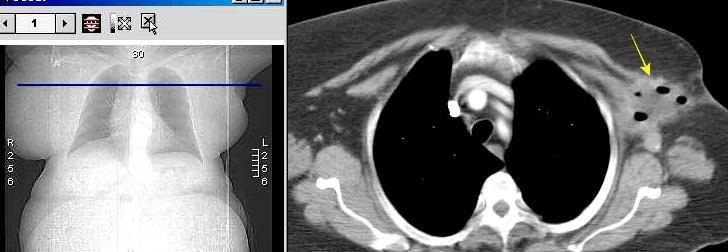

Masa axilar izquierda y derrame pleural derecho. Implantes pleurales, paraespinales . Ganglios en mamaria interna. Linfoma B difuso

Jaffe ES. Diagnosis and Classification of Lymphoma: Impact of Technical Advances.

2005. Masa pulmonar.

Linfoma NH de cél. B. Invasión Transtorácica.

Afectación axilar